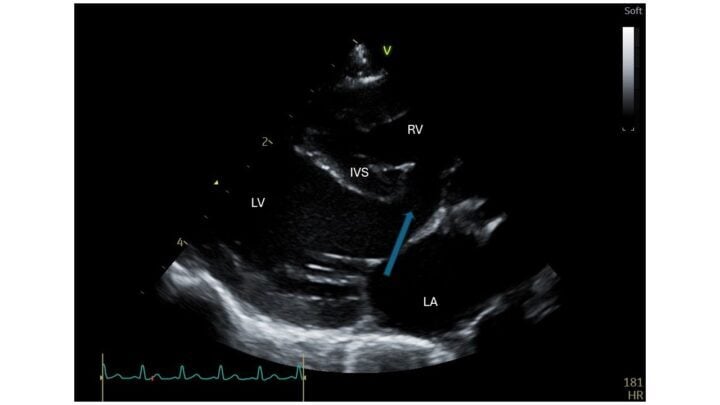

A ventricular septal defect (VSD) is a hole in the interventricular septal wall. It is usually found in the membranous part of the septum, just below the aortic valve. Due to the higher pressures in the left ventricle, blood usually flows from left to right. It is this shunting of blood that causes the heart murmur. Paradoxically, a smaller defect offers more resistance to blood flow and therefore creates a louder murmur, whereas a larger hole offers less resistance, thus causing a quieter murmur. Figure 1 shows a VSD on echocardiography, just below the atrioventricular valves.